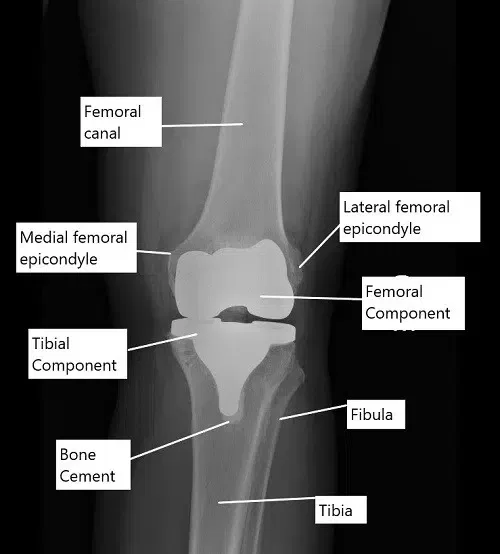

X-ray showing a total knee replacement in AP view.

Knee replacement surgery is most commonly done to treat end-stage osteoarthritis. During the surgery, the bony ends forming the knee joint are replaced with metal alloy prosthetic parts. The lower end of the femur is replaced with a femoral component and the upper part of the tibia is replaced with a tibial component.

The size of the prosthetic metal implants is determined by the size of the bone removed during the surgery. The surgeon cuts the bone to remove the arthritic bone and as well as to correct any deformity caused by arthritis. The implants are capped at the bony ends using special bone cement.

The undersurface of the kneecap (patella) is usually covered by a prosthetic plastic part. A polyethylene plastic spacer is introduced in between the metal parts to smooth the movement and provide stability.